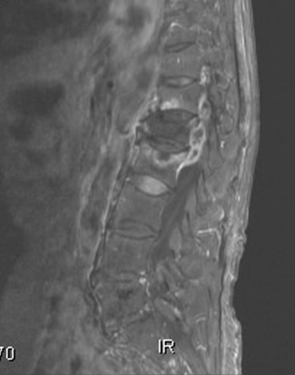

척추 종양(Spine Bone Tumor)

퇴행성 척추 장애

노인성 척추후만증

척추병증

강직성 척추염